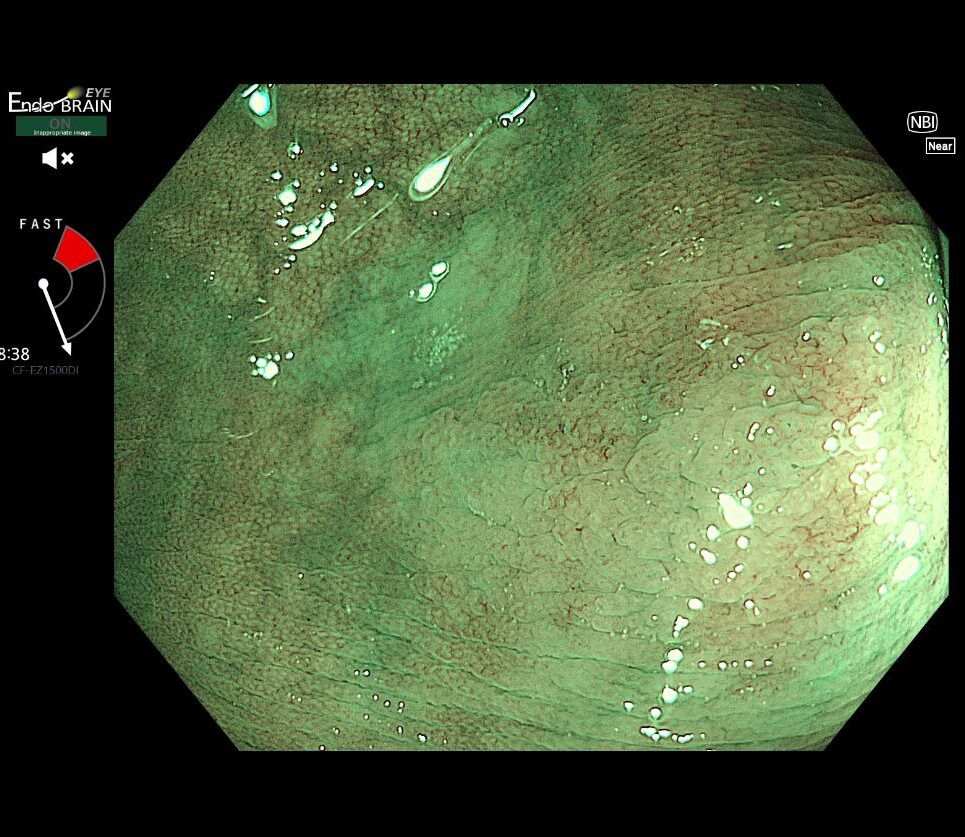

3拡大内視鏡で正体を確認し、その場で切除

違和感を確認するため、スコープを寄せ、拡大内視鏡(NBI観察)で詳細に観察しました。雲のようにぼやけた表面構造(Cloud-like surface)や、腺管の出口が大きく開いた所見(Type II-open pit pattern)を確認し、その場で身体に負担の少ないCSP(コールドスネアポリペクトミー)で切除しました。

拡大内視鏡(NBI観察)

100倍に拡大した所見。SSA/Pに特有の「開Ⅱ型ピットパターン(腺管の出口の広がり)」を明瞭に確認できます。